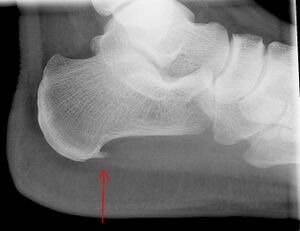

النتيجة العرضية المرتبطة بهذه الحالة هي مهماز العقب، تكلس عظمي صغير على العقب (عظم الكعب)، الذي يتواجد في حوالي إلى 50٪ من المصابين بالتهاب اللفافة الأخمصية.[6] في مثل هذه الحالات، فإن التهاب اللفافة الأخمصية هو الذي يسبب ألم العقب، وليس المهماز نفسه.[13] الحالة هي المسؤولة عن تكوين المهماز على الرغم من أن الأهمية السريرية لمهماز العقب في التهاب اللفافة الأخمصية لا تزال غير واضحة.[12]

التصوير الطبي

لا توجد حاجة روتينية للتصوير الطبي. فهو مكلف ولا يغير عادة كيفية علاج التهاب اللفافة الأخمصية.[15] عندما لا يكون التشخيص واضحًا من الناحية السريرية، فإن الأشعة السينية للرؤية الجانبية للكاحل هي طريقة التصوير الموصى بها لتقييم الأسباب الأخرى لألم الكعب، مثل كسور الإجهاد أو تطور مهماز العقب.[7]

تحتوي اللفافة الأخمصية على ثلاث لفافات - اللفافة المركزية وهي الأثخن بسُمك 4 مم، واللفافة الجانبية بسُمك 2 مم، واللفافة الإنسية بسُمك أقل من 1 مم.[19] نظرياً، يصبح التهاب اللفافة الأخمصية أكثر احتمالًا مع زيادة سماكة اللفافة الأخمصية عند المدخل العقبي. قد يكون مفيداً في التشخيص التصوير بالموجات فوق الصوتية عند سمك يزيد عن 4.5 مم والتصوير بالرنين المغناطيسي عند سمك 4 مم.[20] نتائج التصوير الأخرى، مثل تحديد سماكة اللفافة الأخمصية، غير محددة ولها فائدة محدودة في تشخيص التهاب اللفافة الأخمصية.[13]